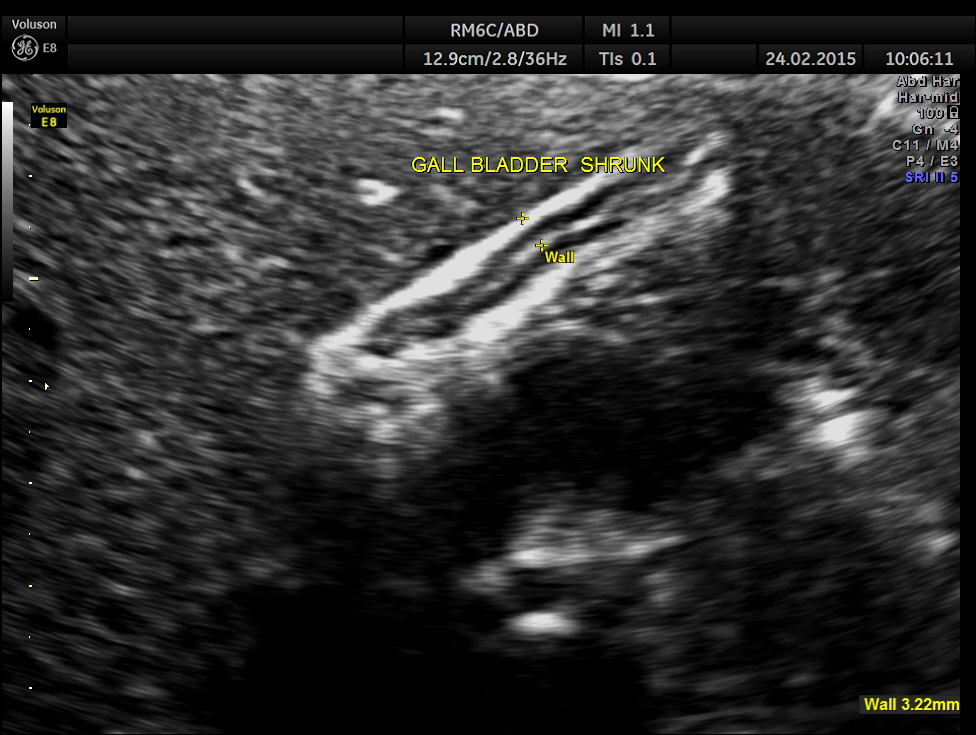

This was a 23 year old young lady , who was evaluated elsewhere for menstrual irregularities . She was reported to have a gallstone . She had no digestive complaints. She went for a 2nd and 3rd opinions, where the gallstone was not seen.She also underwent a CT scan , which reported a shrunk gall bladder and gallstone was not seen. She came to me for another opinion. She was in an over night fasting status ( almost 14 hours after her last meal or drink ).

The following is what was seen.

Completely collapsed and shrunk gall bladder in spite of over night fasting.